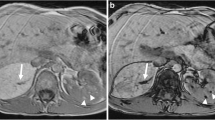

AMLs are not restricted to kidneys and can also be found in other abdominal organs [72], and even in the retroperitoneum [73] (Fig. 5). These lesions have the same imaging characteristics as renal AMLs [72]. Perhaps because they can be more confidently identified, reported cases of extrarenal AMLs tend to have the focal pattern with fatty attenuation on CT images and fat signal on MR images. Contrast enhancement is usually marked in the arterial phase with persistent enhancement during the portal venous phase. Color Doppler US shows punctiform or filiform vascular flow and on gray-scale imaging extrarenal AMLs have been reported as smoothly contoured and echogenic [72].

Two TSC patients with extrarenal fatty masses, presumed to be AMLs. a Axial enhanced CT image shows a heterogeneous but mostly low-attenuation mass causing a mild mass effect in the inferior vena cava (large arrow). A smaller lesion is present in the left hepatic lobe (small arrow). Several similar lesions were also present (not shown). b In another patient, axial enhanced CT image demonstrates a large, diffusely infiltrating fatty mass in the retroperitoneum (arrows). c A conventional renal angiogram (representative image of the left kidney during the nephrographic phase) is normal